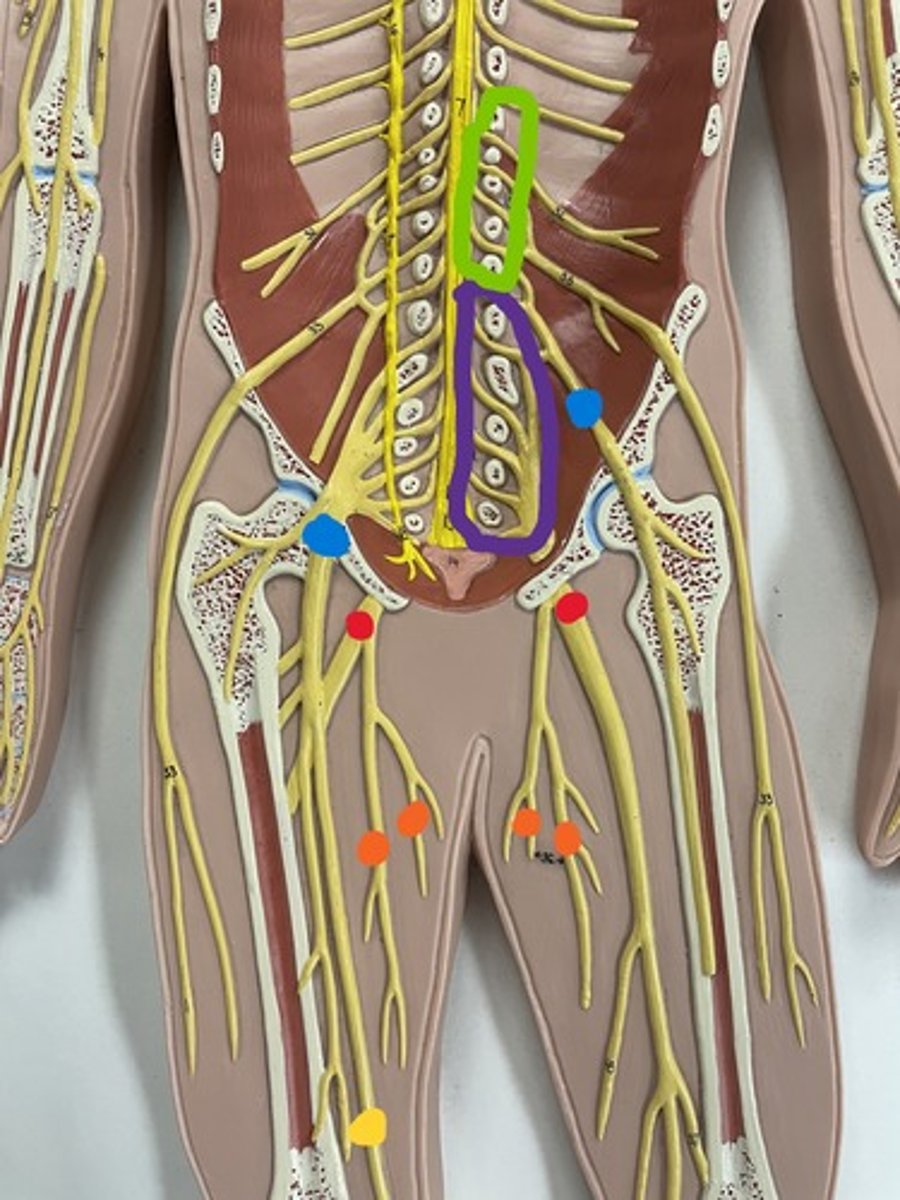

Lumbar plexus

Lumbar plexus

green

Femoral nerve

purple

Femoral nerve

blue

Obturator nerve

yellow

Obturator nerve

orange

Saphenous nerve

yellow

Sacral plexus

purple

Sacral plexus

red

Sciatic nerve

red

Tibial nerve

red

Common fibular nerve

blue